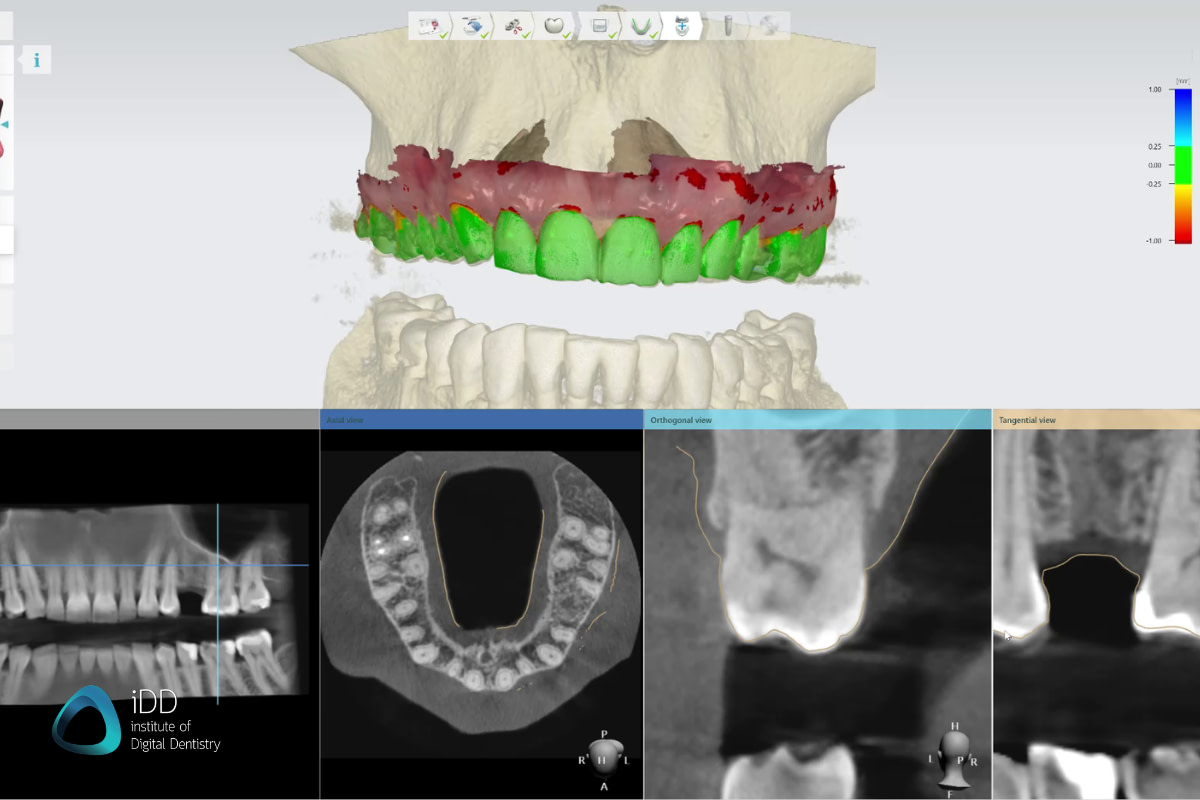

Cone beam CT imaging offers incredibly detailed 3D scans for improved diagnostic abilities and surgical planning.

This comprehensive course covers the fundamentals of dental radiography using current digital imaging technologies. You'll learn proper techniques for capturing diagnostic intraoral and extraoral radiographs with minimal radiation exposure.

Topics include radiation safety, image acquisition, interpretation of normal anatomy and pathology, integration with digital workflows, and patient positioning for optimal imaging.

Gain practical experience utilizing advanced imaging equipment to enhance your radiography skills.